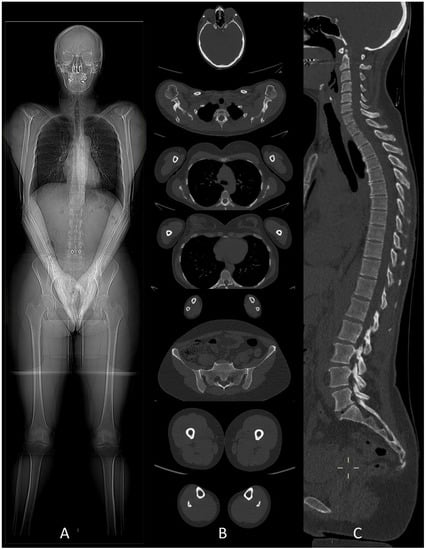

Whole-Body Low-Dose Multidetector-Row CT in Multiple Myeloma: Guidance in Performing, Observing, and Interpreting the Imaging Findings

2. WBLD-CT Protocol and Dose